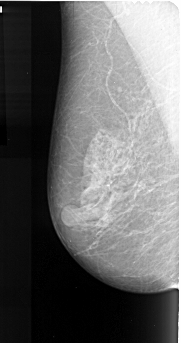

A_1007_1.RIGHT_MLO

RIGHT_MLO LINES 4906 PIXELS_PER_LINE 2491 BITS_PER_PIXEL 16 RESOLUTION 42 OVERLAY

FILE: A_1007_1.RIGHT_CC.OVERLAY

TOTAL_ABNORMALITIES 1

ABNORMALITY 1

LESION_TYPE MASS SHAPE IRREGULAR MARGINS SPICULATED

ASSESSMENT 5

SUBTLETY 4

PATHOLOGY MALIGNANT

TOTAL_OUTLINES 2

BOUNDARY

CORE